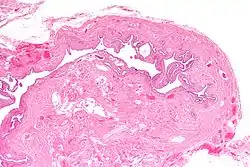

![]() صورة مجهرية لالتهاب برزخ البوق العقد تبين سمك عقدي مميز. صبغة الهيماتوكسيلين واليوزين. صورة مجهرية لالتهاب برزخ البوق العقد تبين سمك عقدي مميز. صبغة الهيماتوكسيلين واليوزين. | |

يتميزالتهاب برزخ البوق العقد بسماكة عقيدية في الغلالة العضلية للجزء الضيق من أنبوب فالوب (البرزخ). وفي الحالات الشديدة، فإنه يؤدي إلى انسداد كامل في تجويف قناة فالوب. ومن غير المألوف أن يحدث على الجانبين في نفس الوقت.[4]